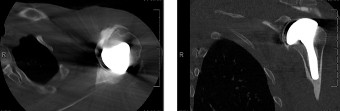

The answer is (B). As the four layers of the lateral rotator interval insert onto the lesser tuberosity of the humerus, they form the “reflection pulley” that forms a sling around the tendon of the long head of the biceps before it enters the bicipital (intertubercular) groove. A tear of the upper part of the subscapularis can disrupt this reflection pulley and destabilize the biceps tendon, allowing it to sublux or even

dislocate out of its groove, usually in a medial direction. If this happens, the intertubercular groove will be empty on MRI. Often, a “pulley sign” will also be seen on MRI when this occurs. This is when contrast material extravasates extra-articularly just over the superior border of the subscapularis tendon on axial images (see Fig. 2–11).

Figure 2–11_Axial T1 MRI. Left: an empty intertubercular sulcus, positive pulley sign (straight _black arrow on left), and dislocated biceps tendon (curved black arrow). Right: fraying subscapularis tendon (arrow). (From Lyons RP, Green A. Subscapularis tendon tears. J Am Acad Orthop Surg. 2005;13(5):353–363.)